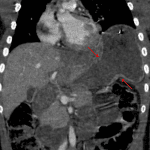

- Left hemidiaphragm rupture with areas of active hemorrhage adjacent to the disrupted diaphragmatic crura and herniation of the stomach into the left hemithorax

- Stomach herniates into the left hemithorax with waist-like narrowing at the diaphragmatic defect and marked submucosal edema of the antropyloric region

Left hemidiaphragmatic rupture with herniation of the stomach into the left hemithorax with areas of active bleeding along the disrupted diaphragmatic crura and possible dissection versus spasm involving the celiac artery.